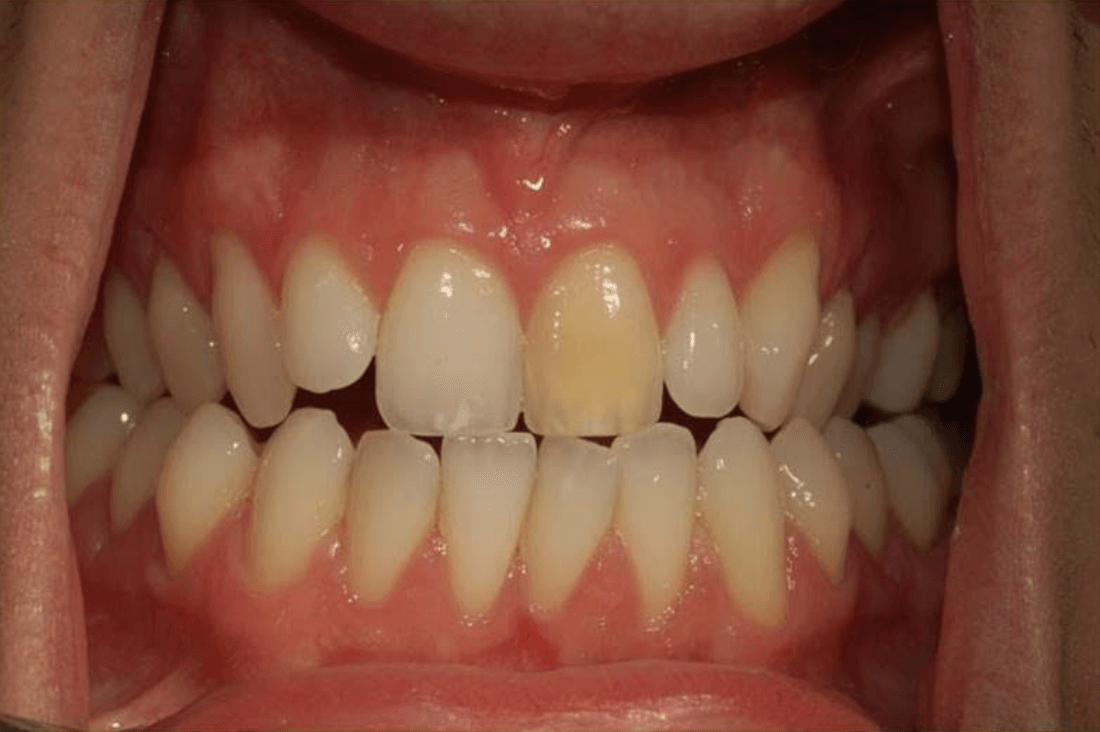

Single Porcelain Crown

Discoloured root canal treated tooth restored with a crown. You can hardly tell!